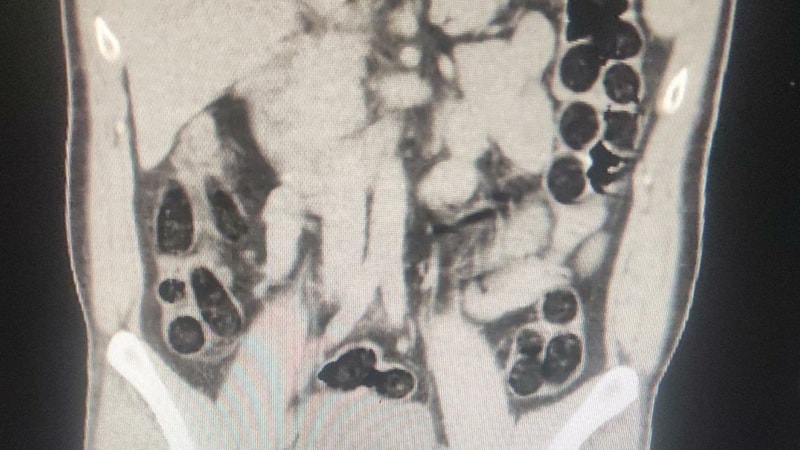

Hastanede çekilen röntgenlerinde birinin midesinde uyuşturucu tespit edildi. Şüphelinin, 76 paket halinde 714 gram eroini doğal yollarla çıkarılması sağlandı.